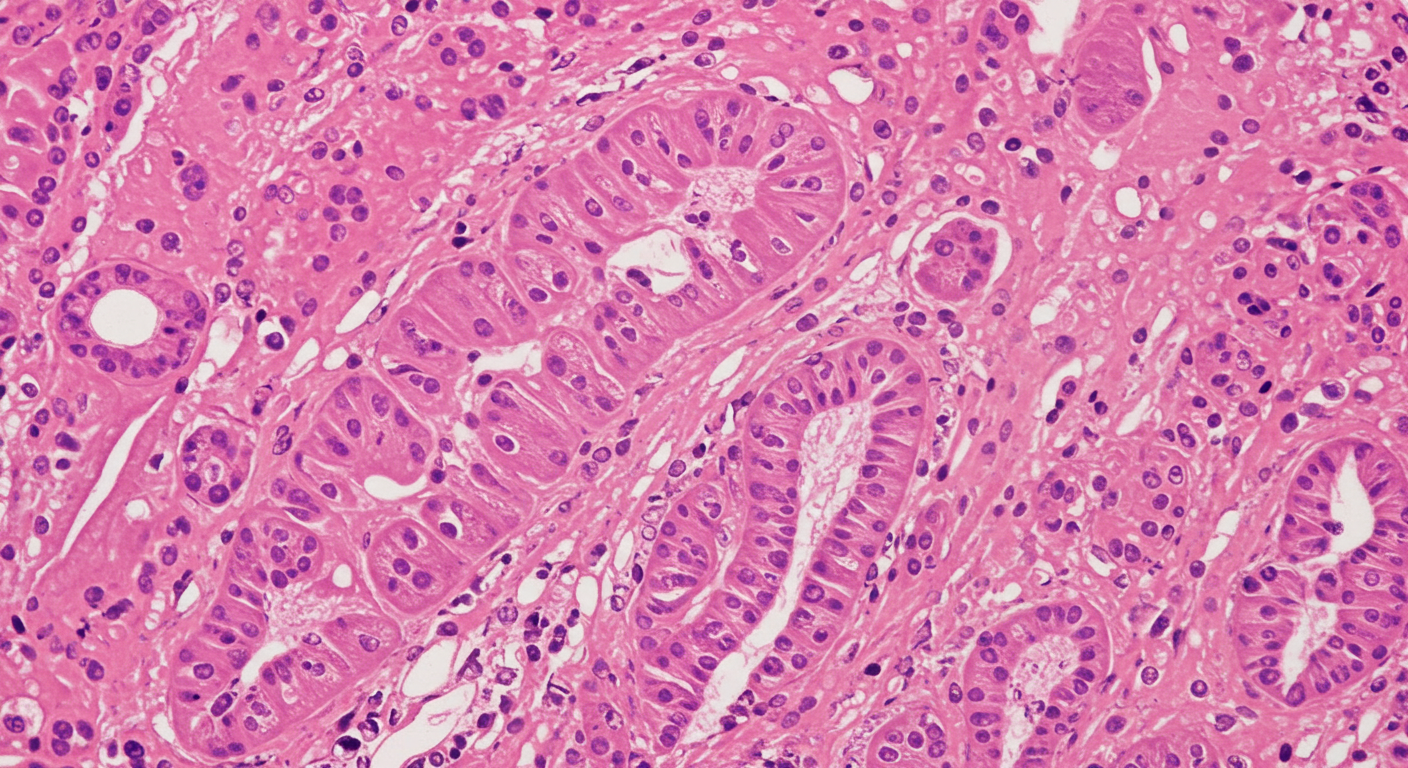

3. 조직검사

면역조직화학 염색으로 KIT(CD117) 양성 여부 확인